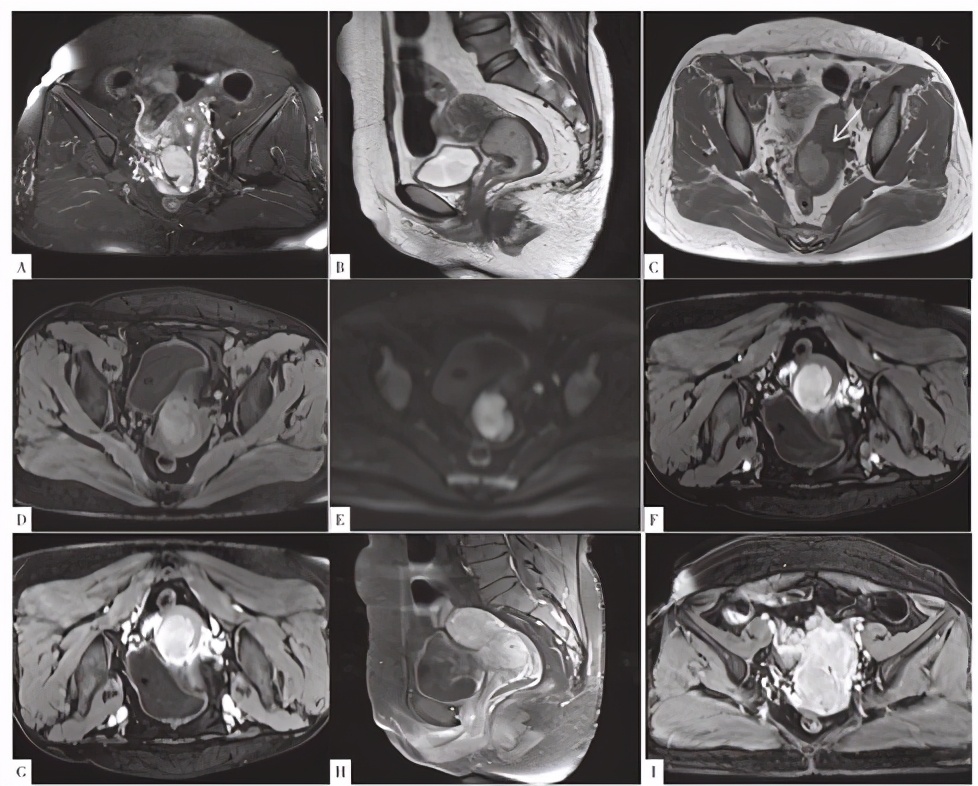

CT检查示:宫颈增粗,见一类圆形等密度占位,增强后动脉期明显均匀强化,静脉期呈等密度,边界尚清,大小31 mm×35 mm,盆腔左侧见数枚肿大淋巴结,见图1。MRI检查示:宫颈见一大小40 mm×35 mm×32 mm的占位,T1WI、T2WI以高信号为主,内见点状T1WI、T2WI低信号影,弥散受限,病灶边缘见流空血管,增强后病灶较均匀、明显强化,界尚清(见图2)。盆腔左侧见数枚肿大淋巴结。

图2 患者MRI检查结果

Figure 2 Result of uterus MRI

目前鲜见针对子宫PEComa的影像学报道,所见报道多认为子宫PEComa不具有特征性影像表现[2,3,4,9]。但本病例的影像表现具有一定的特征性。盆腔见数枚肿大淋巴结,提示子宫占位或为恶性肿瘤的可能。宫颈占位边界较清,明显较均匀强化,病灶边缘见粗大的血管,提示病灶血供丰富。肿瘤实性部分在MRI平扫图像上呈现出特征性的T1WI、T2WI高信号表现,可能与肿瘤细胞内黑色素颗粒含量有关,本例患者病理检查图像可见一定数量的黑色素颗粒。研究发现,黑色素瘤可因黑色素含量不均匀而表现为混杂信号。ISIKLAR等[10]将颅内黑色素瘤根据黑色素含量不同分为4种类型:(1)黑色素型,T1WI呈高信号,T2WI呈低信号;(2)无黑色素型,T1WI呈低或等信号,T2WI呈高或等信号;(3)混合型,表现多变;(4)血肿型,只表现为出血的MRI特征。当黑色素瘤中黑色素细胞含量为10%时,才会出现黑色素顺磁性所致的典型黑色素瘤MRI特征,即T1WI呈高信号表现,T2WI呈低信号表现,具有高度特异性[10,11];无黑色素型、混合型及血肿型黑色素瘤均属于非典型性黑色素瘤,临床上罕见[12,13]。子宫PEComa与黑色素瘤一样含有黑色素颗粒,故笔者推测本例PEComa患者的MRI表现与肿瘤细胞内黑色素颗粒的含量密切相关。

本例子宫颈恶性PEComa患者应与下列疾病鉴别:(1)宫颈癌:表现为接触性出血,T1WI呈等低信号,T2WI较高信号,增强扫描后肿瘤于动脉期强化明显,门脉期及延迟期肿瘤呈轻度强化,与正常子宫肌层相比呈相对低信号,而本例子宫颈恶性PEComa患者无接触性出血表现,MRI表现亦不符合宫颈癌表现;(2)子宫颈癌肉瘤:子宫癌肉瘤瘤内异质性明显,常伴有坏死、囊变及出血,使得肿瘤信号混杂、强化不均,与本例患者较均匀强化的子宫颈恶性PEComa不同;(3)子宫颈肉瘤:T1WI呈等低信号,T2WI呈较高信号,分叶状,信号不均,常可见中心大片坏死区,增强扫描不均匀强化,边界不清,以囊性为主的病灶,其内小囊数目多且呈网格状改变,可作为子宫肉瘤的一种特征性表现,易可与本例子宫颈恶性PEComa鉴别;(4)子宫颈肌瘤伴变性:红色变性、脂肪、黏液变性表现为T1WI、T2WI高信号,但信号不均匀,脂肪变性区呈低信号,黏液变性区域增强无强化,且不伴有盆腔淋巴结肿大,可与子宫颈恶性PEComa鉴别。综上,以下影像表现结合病史可提示存在子宫PEComa的可能:(1)T1WI高信号;(2)宫颈肿瘤密度/信号相对均匀,强化均匀;(3)增强扫描中心或边缘见粗大迂曲强化血管。然而对于无特征性影像表现的子宫PEComa,仅能依靠病理诊断,免疫组化尤其重要[14]。